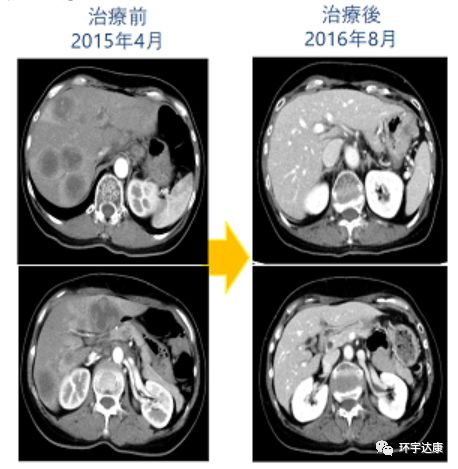

一位晚期肠癌肝转移的患者,选择化疗联合WT1树突细胞疫苗治疗,体内的CTL(细胞毒性T细胞)含量治疗前为0.01%,而在进行7次树突细胞治疗后,体内的CTL的含量竟然达到0.33%!2016年11月,CT扫描结果显示病灶全部消失了,病理检测结果也证实了患者达到了完全缓解状态。